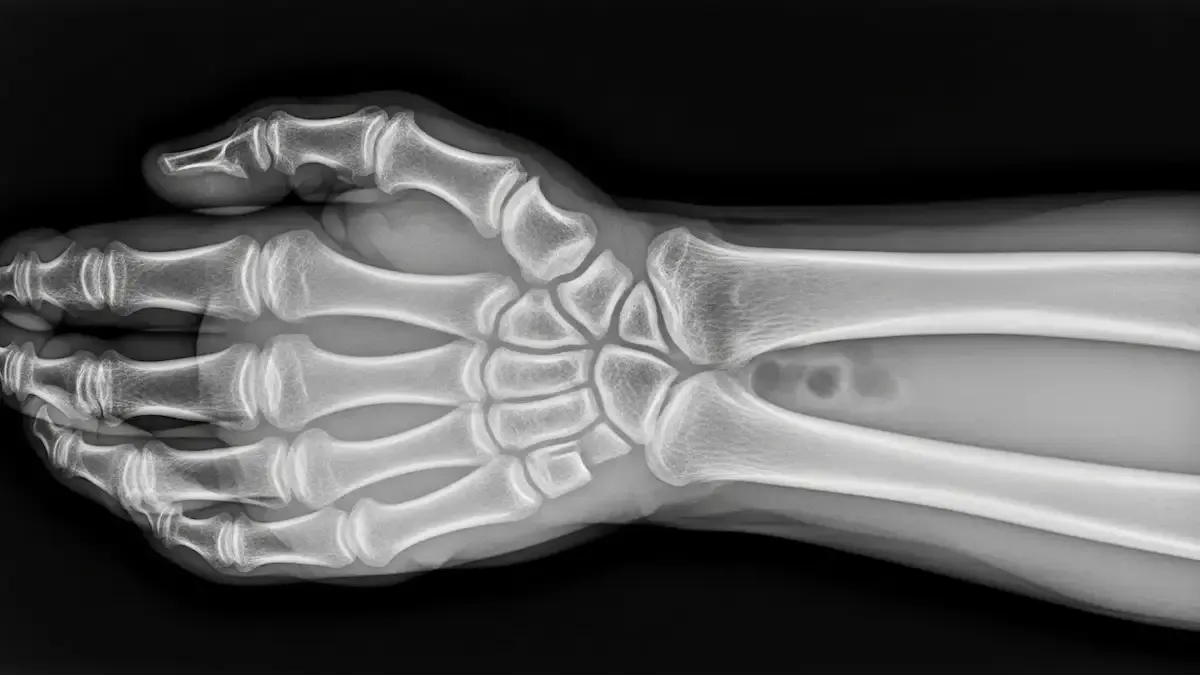

O diagnóstico da artrose do punho parte da avaliação clínica, considerando queixas de dor, sensação de rigidez e redução da mobilidade articular.

Exames de imagem, como radiografia, confirmam o desgaste articular, enquanto a ressonância magnética pode ser solicitada para avaliar cartilagem, ligamentos e estruturas associadas.